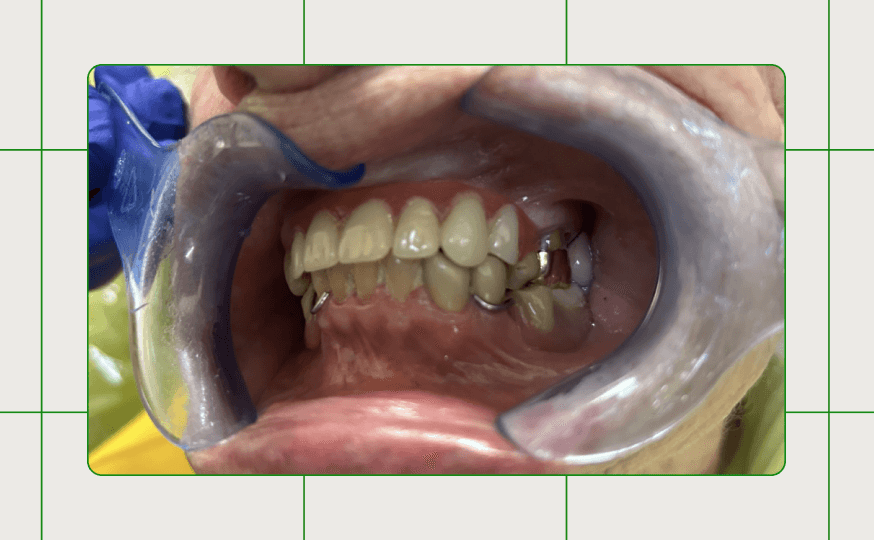

Accommodating the patient’s requests for palatal coverage and non-metal material, Duraflex partial was used to restore sites #7-12.